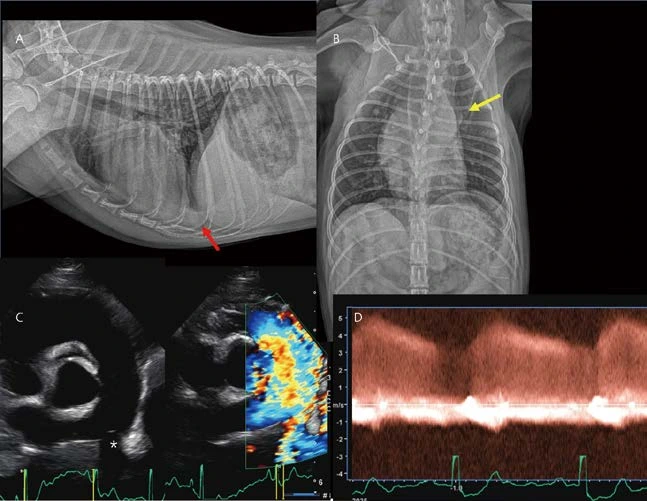

14살 중성화 수컷 3.1kg Poodle 환자가 호흡곤란으로 응급 내원하였습니다. SpO₂는 w/o O₂ 76%, w/ O₂ 99%였고, 심청진에서 grade 4 이상의 left apical systolic heart murmur가 crackle lung sound와 함께 확인되었습니다. 흉부방사선 검사에서 cardiomegaly with pulmonary congestion이 관찰됩니다. 또한 perihilar region과 양쪽 후엽에서 폐포성 침윤이 관찰됩니다(A, B). 심초음파에서 MMVD(ACVIM stage C; LAD index 1.97, LA/AO ratio 2.73, MV e peak velocity 1.29m/s, 약간 감소된 MR peak velocity, asymmetric pointed MR flow profiles)(C, D), 폐초음파에서 confluent B lines(B profile, pulmonary edema)가 관찰됩니다(E). 환자는 MMVD로 인한 cardiogenicpulmonary edema로 진단되었고, 응급중환자실에서 입원치료 후 잘 퇴원하였습니다. 약 1년 6개월 후 다시 호흡곤란, 졸도, 기력저하로 응급 내원하였습니다. 이전 흉부방사선 검사와 비교 시, globoid cardiomegaly with sharp contour 소견이 관찰되며, 폐혈관은 오히려 직경이 작게 측정됩니다(F, G). 심청진에서 muffled sound, 노력성 호흡, 혈압 80mmHg로 측정됩니다. 심초음파에서 심낭수가 관찰되며, 이로 인해 RA, RV 뿐만 아니라 좌심까지 collapse되어 관찰됩니다.(H *) Cardiactamponade 상태로 확인되었고, 바로 수액을 공급하면서, 낮은 속도로 조심스럽게 심낭수 천자(약 20ml의 혈액성 심낭수)를 진행하였습니다. 심초음파에서 tumor, 혈전 등의 소견은 관찰되지 않았고, 심낭수의 세포학적 검사 및 배양에서도 이상 소견은 확인되지 않았습니다. 환자는 다행히 cardiac tamponade 상태를 잘 회복하였고(I, 심낭수 천자 직후), 다시 MMVD 심장 내복약으로 관리 받다가 약 2개월 후 집에서 급사하였다고 합니다.